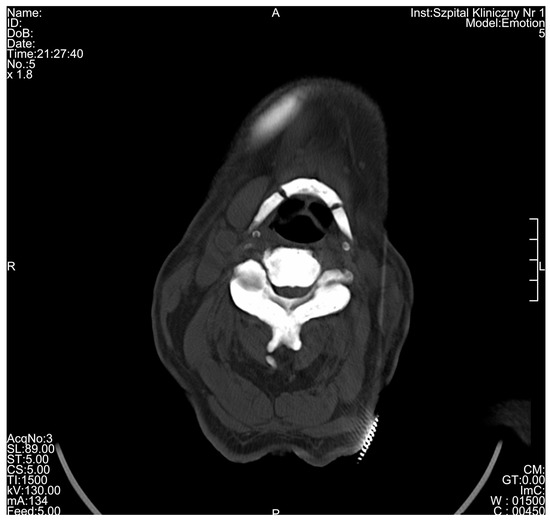

3. Results

| Radiological Feature | ADO Type I | ADO Type II | ADO Type III | Presented Case |

|---|---|---|---|---|

| General osteosclerosis | + | – | + | + |

| Skull vault osteosclerosis | + | – | + | + |

| Skull base osteosclerosis | – | + | – | + |

| Sandwich vertebrae (Ruger–Jersey spine) | – | + | – | + |

| Bone within bone | – | + | + | + |

| Hyoid sclerosis | – | – | – | + |